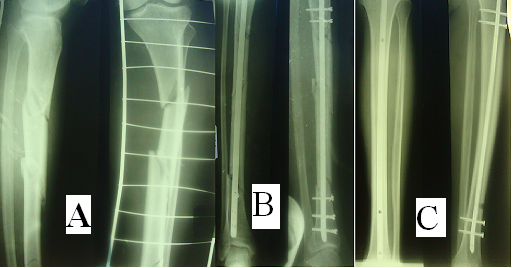

Классификация переломов диафиза бедренной кости: Иллюстрации и информация